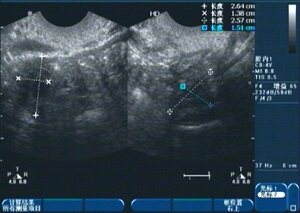

幼稚子宫患者小林,29岁,一直无月经来潮。2006年因无月经在当地好的医院医院治疗,采取了人工周期治疗,用药第一个月来月经了,此后就间断采取人工周期治疗4年,经过治疗后,多次复查,子宫也只是略有增大,但仍达不到正常生育要求,且停药后月经再也没来过,做b超检查仍显示幼稚子宫,仍无法怀孕。

小林先后到过北京、广州、深圳等多地医院求医,均没有达到理想效果。2014年,小林又打听到杭州红房子妇产医院能治疗幼稚子宫,她抱着试一试的心态来到杭州。石女之母费旭红主任通过阴道四维彩超检查,提示:幼稚子宫。垂体兴奋实验检查提示:低促性腺性功能低下。费主任说:这个病是可以治疗的!